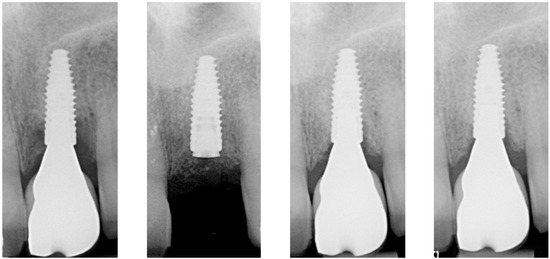

| Radiographic bone level at Tpre mesial (mm) | 5.6 | 3.8 | 1.7 |

| Radiographic bone level at Tpre distal (mm) | 7.6 | 4.2 | 3.2 |

| Radiographic bone level at T2 mesial (mm) | 0.4 | 3.5 | 0.0 |

| Radiographic bone level at T2 distal (mm) | 1.8 | 3.9 | 0.0 |

| Radiographic bone level at T6 mesial (mm) | 2.8 | 3.4 | 1.1 |

| Radiographic bone level at T6 distal (mm) | 3.5 | 0.7 | 2.5 |

| Radiographic bone level at T12 mesial (mm) | 2.3 | 2.5 | 1.7 |

| Radiographic bone level at T12 distal (mm) | 3.5 | 1.5 | 2.5 |